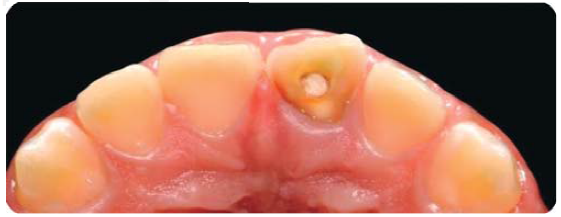

En la exploración clínica extra e intraoral sólo se observa la fractura dental (Figura 26), en la radiografía se observa el tratamiento de sistema de conductos (Figura 27).

Fractura complicada de corona del diente 21, radiográficamente se observa un diente despulpado con tratamiento de sistema de conductos y sin lesión periapical; periodontalmente presenta gingivitis inducida por placa dentobacteriana (Figura 28).